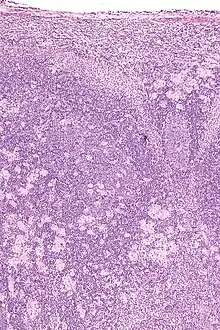

High magnification micrograph of toxoplasmosis -

Brain biopsy-High magnification micrograph of toxoplasmosis -

Immunohistochemistry displaying positive Toxoplasma gondii trophozoites in a brain biopsy of a HIV immunocompromised individual

Real-time PCR is useful in pathogen detection, gene expression and regulation, and allelic discrimination. This PCR technique utilizes the 5' nuclease activity of Taq DNA polymerase to cleave a nonextendible, fluorescence-labeled hybridization probe during the extension phase of PCR.[63] A second fluorescent dye, e.g., 6-carboxy-tetramethyl-rhodamine, quenches the fluorescence of the intact probe.[63] The nuclease cleavage of the hybridization probe during the PCR releases the effect of quenching resulting in an increase of fluorescence proportional to the amount of PCR product, which can be monitored by a sequence detector.[63] Lymph nodes affected by Toxoplasma have characteristic changes, including poorly demarcated reactive germinal centers, and scattered epithelioid histiocytes.[64]